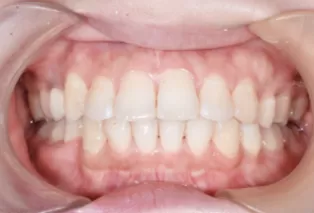

Intraoral photos after treatment